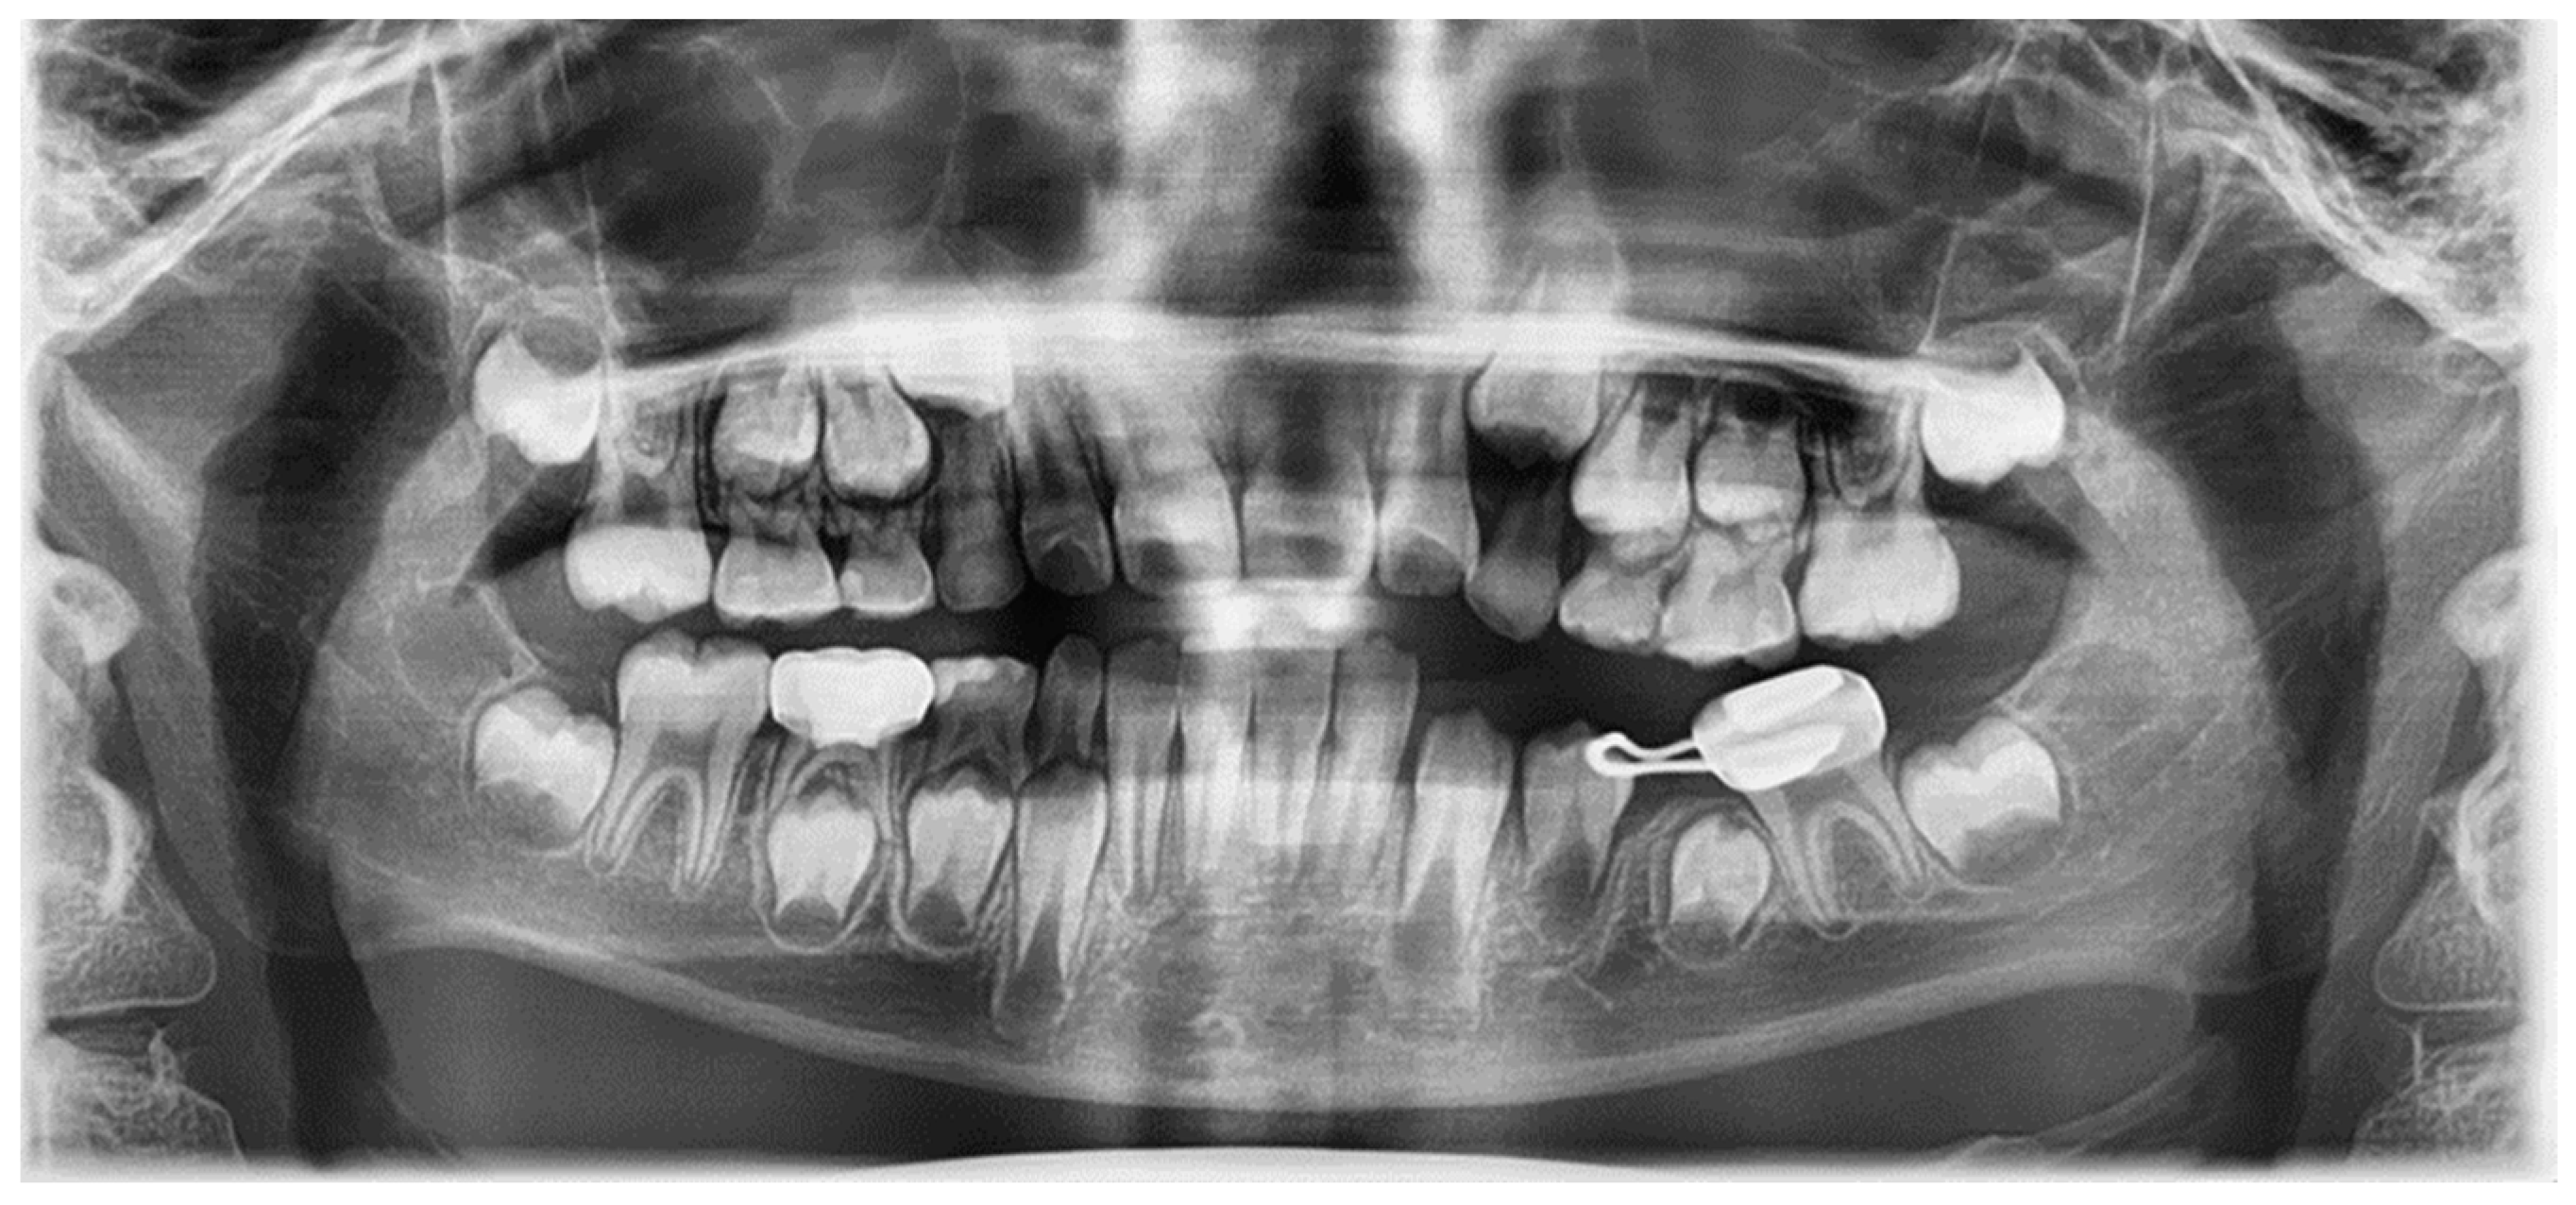

An 8-year-old girl was referred to the Department of Pediatric Dentistry of Kyung Hee University Dental Hospital at Gangdong from a local dental clinic for the treatment of a cystic lesion in the left mandibular primary molar area. Her medical history was unremarkable. According to the referral from the local dental clinic, her dental history was a pulpectomy with root canal filling with Vitapex® and restoration with a stainless-steel crown on the left mandibular primary molar 3 years ago. An endodontic retreatment was performed due to a recurrent periapical abscess that occurred 16 months after the initial treatment at the local clinic. Nevertheless, due to the residual periapical lesion and severe tooth mobility, the teeth were extracted one year after the retreatment at the local clinic. Radiological examination revealed a well-defined osteolytic lesion involving the premolars and radiopaque overfilling materials (Vitapex®) around the involved premolars (Figure 4a). Cone-beam computed tomographic (CBCT) view, cortical bone thinning, and expansion of the lesion were observed (Figure 4b).

Figure 4.

Initial visit: (a) panoramic radiograph; (b) cone-beam computed tomography. The cystic lesion around the successive left mandibular premolars can be seen, and extruded canal filling materials are also observed.

Due to the large size of the cyst, marsupialization to preserve the permanent teeth was planned. Under general anesthesia, marsupialization and incisional biopsy were conducted. The drain was inserted into the cyst cavity and sutured to maintain the openness of the lesion. The biopsy result was a benign cyst with an abscess.

Six months after treatment, the cyst size was significantly reduced, and the premolars had erupted (Figure 5). Thirty months after treatment, the extruded canal filling material remained around the roots of the erupted left mandibular premolars (Figure 6). The patient showed no clinical symptoms.

Figure 5.

Six months after marsupialization: (a) periapical radiograph; (b) intraoral photo. Left mandibular premolars have erupted and extruded canal filling materials still exist.

Figure 6.

Thirty months after marsupialization. Panoramic radiograph. The extruded canal filling materials remain around the root of the erupted left mandibular premolar.